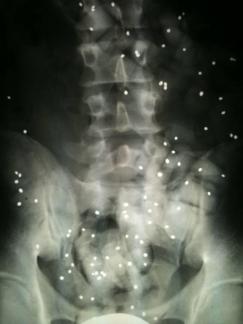

Wie wichtig sind Röntgenbilder?

Röntgenbilder sind wichtig, aber häufig überbewertet.

Wenn keine Hinweise auf eine scherwiegende Erkrankung (spezifische Rückenschmerzen) vorliegen dann ist die genaue Befragung und die Untersuchung wichtiger als Röntgenbilder.

Wenn Sie Röntgenbilder mitgebracht haben werden wir und diese gemeinsam mit Ihnen anschauen.

Nicht selten erwidern Patienten auf die Frage, was sie zu uns führt, mit der Antwort: "Schauen sie die Bilder an, ich habe 3 Bandscheibenvorfälle!".

3 relevante Vorfälle sind selten und solche Aussagen kommen zustande, wenn die Röntgenbefunde fehlinterpretiert werden.

Lesen Sie folgenden Kernspinbefund und Sie sind überzeugt so richtig krank zu sein:

Steckfehlstellung mit steilgestellter Lendenwirbelsäule

Initiale Osteochondrose Th 10-12 und L 1-L4, ausgeprägt bei L 4/5 teilweise erosiv mit Deckplattenödem Modik 1 und ventralen osteophytären Abstützreaktionen

Intraspinale Bandscheibenprotusionen L 3/4 und L 5/S1.

Bandscheibenprolaps L 4/5 medio bi-paramedian mit Pellottierung des Duralsackes und Kontakt zu den Wurzeln L5 beidseitig rechts betont.

Spondylarthose L 4/5 beidseitig und initial L 5/S1 beidseits. Deutlich verdickte Gelenke mit beginnender Einengung des Spinalkanals

Kombinierte Foramenstenosen L 4-S1 beidseits, besonders L 4/5 rechts

In der T2 Wichtung vermindertes Signal der unteren lumbalen Bandscheiben als Hinweis auf Wasserverlust mit „black disk“

Der Befund kann für einen durchschnittlichen 50jährigen durch 2 Worte ersetzt werden:

Altersentsprechender Befund.

Der Radiologe beschreibt auf den Bildern alles was er sieht, und das sind natürlich auch Verschleißerscheinungen.

Wenn ein Gutachter mein Auto (150.000km) beurteilt, wird ein mehrseitiger Bericht dabei herauskommen. Dass ich aber damit dennoch im Jahr problemlos 30.000km fahre ist davon unbenommen.

Verschleiß ist normal; meistens macht das keine Probleme.

Bei jeder Bewertung eines Befundes ist die Relevanz wichtig. Darum werde ich die Röntgenbilder mit Ihnen besprechen.